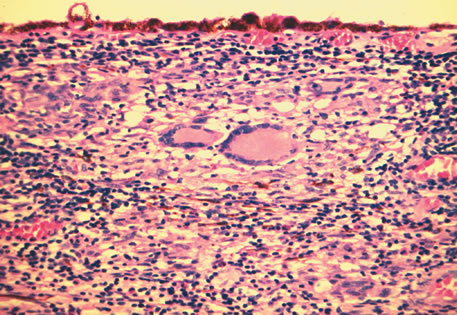

Children with juvenile rheumatoid arthritis (JRA) develop inflammation of the iris and ciliary body. The pauciarticular form of JRA (fewer than five joints involved) accounts for the majority of cases associated with iritis. The majority of patients with iridocyclitis and JRA are antinuclear nuclear antibody (ANA) positive. Rheumatoid factor assay is usually negative. Chronic inflammation may result in peripheral anterior synechia, posterior synechia, cystoid macular edema, vitreous debris and opacification, and chronic band keratopathy. Secondary glaucoma and cyclitic membranes may also be seen. Histologically, inflammation may be seen primarily in the iris (Fig. 11) and ciliary body and consists of nongranulomatous chronic inflammatory infiltration. The infiltrate often consists of lymphocytes and plasma cells. Russell bodies may be common in chronic cases.81,82 Other disorders with a similar nongranulomatous inflammation of the uveal tract include ankylosing spondylitis, Reiter's syndrome, ulcerative colitis, and Behçet's disease.

Fig. 11. Juvenile Rheumatoid Arthritis. Non-granulomatous chronic inflammation is present in the iris. The inflammatory infiltrate contains plasma cells. (Hemotoxylin-eosin ×140.)